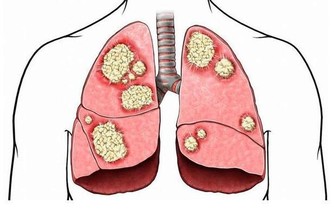

4 利尿通乳 萵苣鉀含量大大高於鈉含量,有利於體內的水電解質平衡,促進排尿和乳汁的分泌。對高血壓、水腫、心臟病人有一定的食療作用。 5 強壯機體、防癌抗癌 萵苣含有多種維生素和礦物質,具有調節神經系統功能的作用,其所含有機化含物中富含人體可吸收的鐵元素,對有缺鐵性貧血病人十分有利。 萵苣的熱水提取物對某些癌細胞有很高的抑制率,故又可用來防癌抗癌。